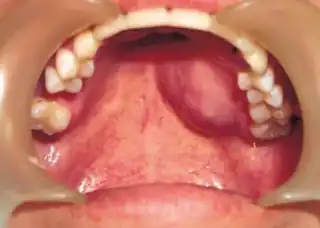

![]() ![]() | |

| Top: Ewing sarcoma of the thigh bone on a child's CT scan Bottom: Extraskeletal Ewing sarcoma of the hard palate | |